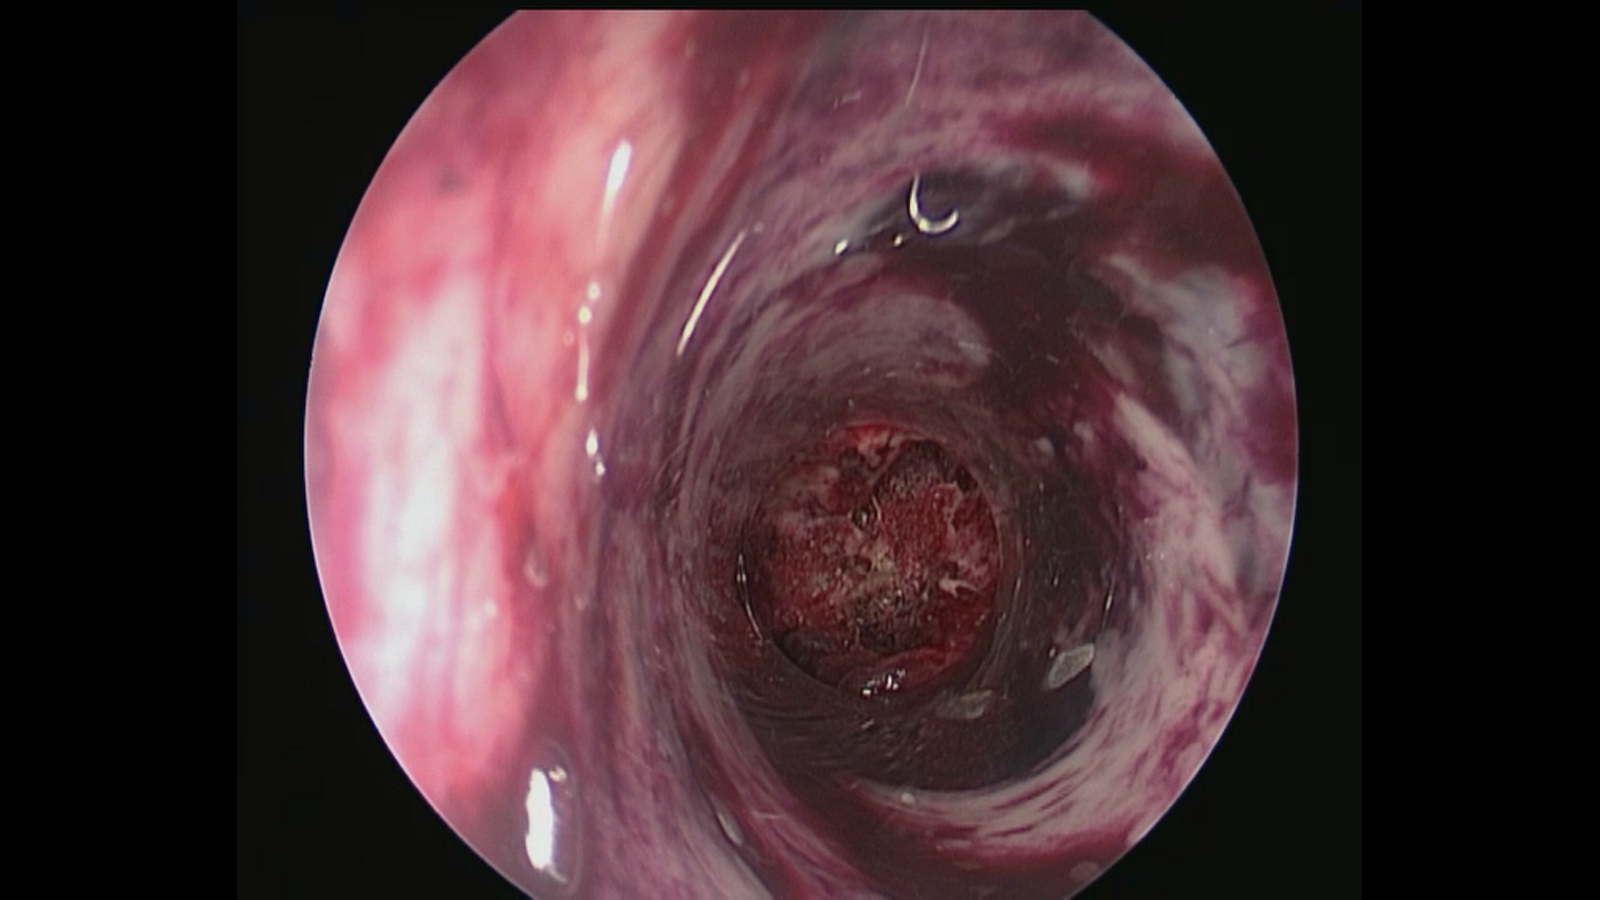

手术入路:神经内镜辅助右丘脑出血清除术。